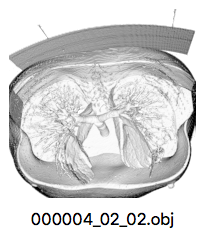

ct画像から3Dモデルを作った話

概要

ct画像から3Dモデルを作ってみた。問題設定

映画(例えばインビジブル)とかで、よく人体の3Dモデルで内蔵とかを模写する場面とかってあるじゃないですか。今回やってみたのは、その3Dモデルをct画像を重ねる事で作れないかと思い、やってみました(導入が雑だが、やった理由なんて適当で良いよね?)。

やった事

- データ(一人の人体から作成したct画像)を収集

まずは、データ集めから。

探してみると、ここが良さそう。

ここから適当に良さそうなデータを集めて、lung_listフォルダに入れた(以下画像参照)。

- ct画像から3Dモデルを作成

ct画像から3Dモデルへ変換(ボリュームレンダリング)するツールを調べてみると色々ありそう。

この中から今回はFijiを使って見ることにした。

ダウンロードページはこちらから。

操作方法はここ。

操作方法のページの 'ファイルの読み込み(連番画像の場合)' の項目を参考に、先ほどのプログラムの結果が入ったフォルダ(上記の例だとlung_list_conv)の中から、一人のct画像が入ったフォルダ(上記の例だと000004_02_02)を読み込む。

その後、'ボリュームレンタリング' の項目を参考に3Dモデルを作成できる。

作成したら、出てきたウィンドウ中の3Dモデルをクリックしてモデルを選択。

その後、ツールウィンドウをクリックし、PC画面上部のメニューバーから File -> Save As -> WaveFront .OBJ ... の順番でクリックすれば、モデルをobjファイルとして保存出来る。

上記画像では少し分かりにくいが、作者は実際にUnity上で読み込ませる事が出来たので良しとする。